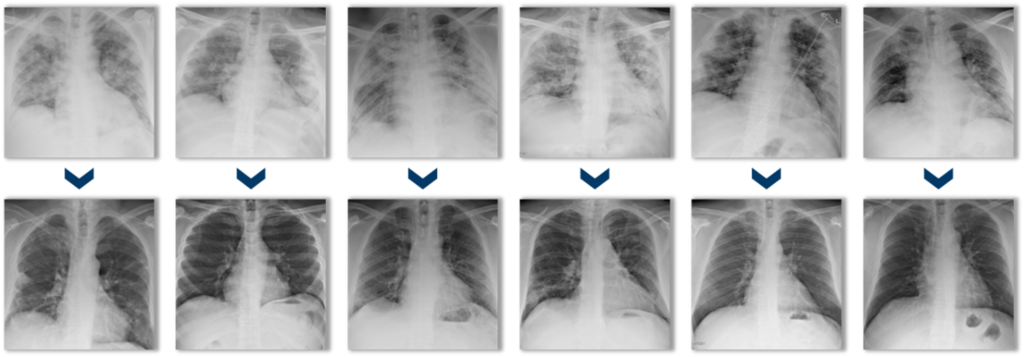

צילומי חזה של שישה מטופלים לפני טיפול במזנקיור (שורה עליונה) וכ-30 יום לאחר מכן (שורה תחתונה)

(קרדיט: מתוך הדוחות הכספיים של החברה)

צילומי חזה של שישה מטופלים לפני טיפול במזנקיור (שורה עליונה) וכ-30 יום לאחר מכן (שורה תחתונה). לפני הטיפול, ריאותיהם של החולים עמוסות בתסנינים דלקתיים (עודף נוזלים, תאי חיסון וחלבונים) החוסמים נשימה תקינה. לאחר הטיפול, הדלקת מתנקה.